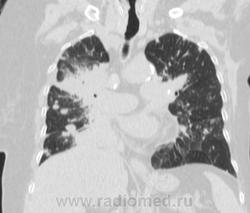

Метастатическое поражение легких.

Пожилая женщина, 76 лет находится на стац.лечении, провели СКТ дообследование.  Сопут- сr левой молочной железы. Такие множественные

поражения  в легких встречаются не часто.

Раннее несколько лет назад оперирована по поводу рака левой молочной железы.